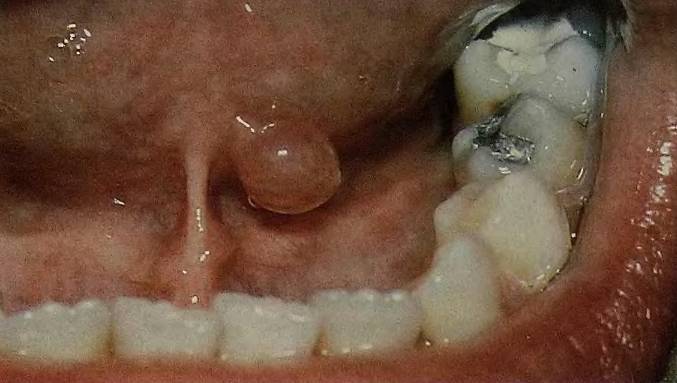

Пациенты жалуются на прозрачные или кровяные пузырьки, мелкие высыпания или уплотнения на небе. Образования могут возникать на верхней части языка, под ним, на уздечке или в области перехода. С увеличением размера уплотнение меняет форму и цвет, становясь круглым, напоминая песочные часы или приобретая белый, синий или красный оттенок.

Наиболее распространенной является ранула — ретенционная киста. Она:

- располагается под слизистой оболочкой;

- чаще всего возникает под языком;

- небольшого размера;

- плотная и упругая на ощупь;

- содержит жидкость внутри;

- не вызывает болевых ощущений.

Ранула может периодически опорожняться при легком повреждении стенки, например, при контакте с зубами, но жидкость снова накапливается.